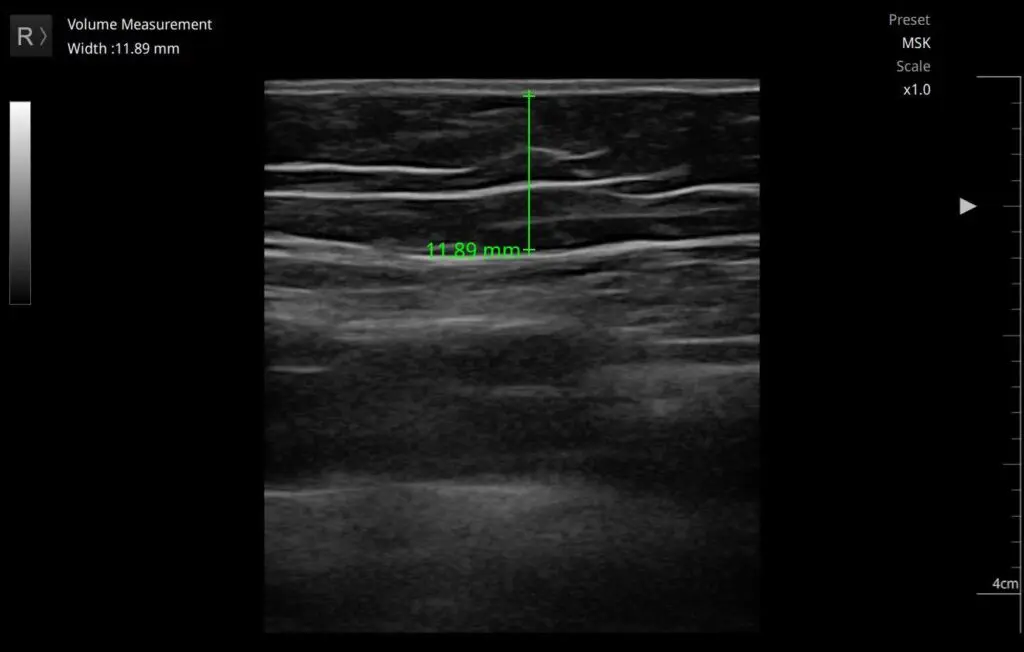

Pomiar grubości tkanki tłuszczowej

Ultrasonografia jest również skuteczną metodą w ocenie grubości tkanki tłuszczowej, co ma znaczenie w diagnostyce otyłości oraz w monitorowaniu efektów terapii redukcji tłuszczu.

Technika ta pozwala na precyzyjny pomiar wspomnianej tkanki w różnych częściach ciała, a także umożliwia ocenę jej rozmieszczenia. Badania wykazały, że USG jest szczególnie pomocne w ocenie cellulitu, gdyż pozwala na identyfikację nieprawidłowości w tkance tłuszczowej.(6)